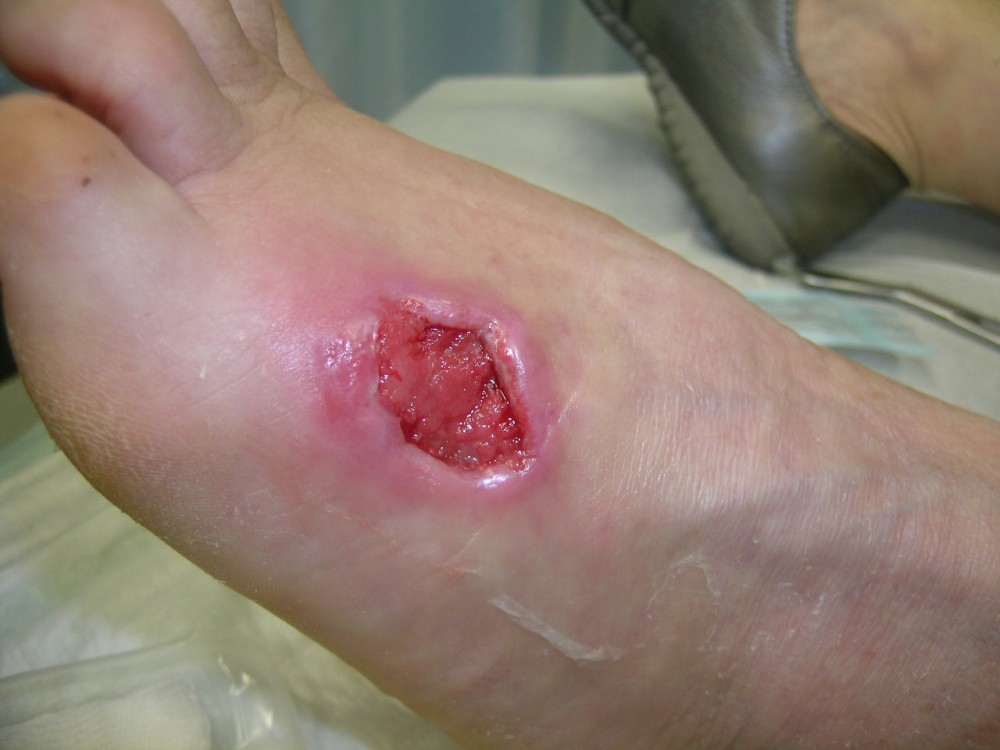

Motivo de consulta: Paciente que acude el 12-8-2013 a nuestro centro asistencial con una fuerte contusión en pie izquierdo. Es trasladada por un compañero de trabajo. Tras ser vista y realizada exploración radiológica negativa. Se realiza vendaje compresivo y se le deja con carga relativa de EI Izda. con ayuda de bastones ingleses. Tto. analgésico y reposo. A la semana (19-8-2013) en la revisión refiere dolor intenso en antepié izquierdo desde hace 3 días. El vendaje aparece manchado. Al retirar vendaje aparece zona necrosada en cara externa del antepié izquierdo. Tras interconsulta con cirugía plástica se decide realizar desbridamiento bajo A/L. Antecedentes personales: -Alérgica a METAMIZOL y PENICILINA. - No refiere enfermedades. - Vacunada Difteria- Tétanos. - No fumadora. - No patología ginecológica. Ha tenido 1 parto a los 26 años (sin complicaciones)

• 8. Higiene / Integridad piel y mucosas: Herida ulcerada y necrosada en cara externa de antepie izquierdo de 5 cm. de diámetro y 2 cm. de profundidad

Secreción purulenta Necrosis Granulación Disminución del tamaño de la herida

La paciente acudió el 12-8-2013 con una contusión fuerte en antepié izquierdo que fué tratada con inmovilización, analgesia y tratamiento anticoagulante con heparina de bajo peso molecular. y descarga de la extremidad. A la semana acude a revisión presentando dolor intenso y zona de necrosis en supercie de contusión. El mismo día de revisión (19-8-2013) se realiza consulta con cirujano que realiza desbridamiento quirúrgico bajo A/L quedando una herida con buen fondo de granulación de 5 cm. de diámetro x 2 cm. de profundidad. Se mantiene tratamiento anticoagulante, se refuerza tratamiento analgésico y se instaura tratamiento antibiótico. Se pautan 3 curas semanales. Se hace control semanal de todos indicadores retirando el tratamiento antibiótico a la 3ª semana, se suspende el tratamiento anticoagulante a la 4ª semana, se suspende el tratamiento analgésico a la 7ª semana. Produciéndose la curación de la herida a la 8ª semana. Queda pediente de revisión al año del accidente por posibles secuelas cicatriciales.